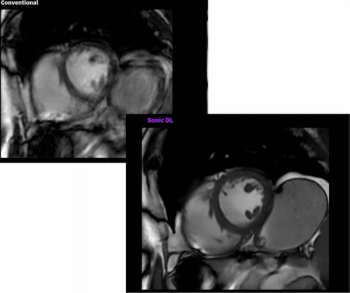

Powered by deep learning technology, Sonic DL reportedly facilitates the acquisition of cardiac magnetic resonance imaging (MRI) scans at 12 times the speed of conventional MRI systems.